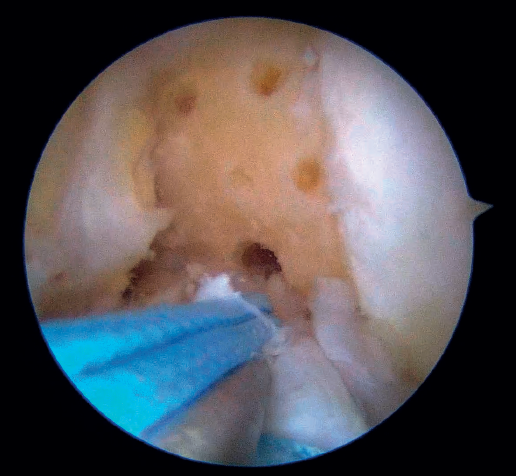

The tibial tunnel is prepared with a guide inserted through the cannula of the anteromedial portal, passing a 2.4 mm cannulated drill from the medial cortex of the tibia to the most anterior region of the tibial footprint of the ACL, taking care to damage the ligament fibers as little as possible during this step.

Once the tunnel has been drilled, the guide is removed from the inside of the drill and another retriever thread is inserted through it. This thread is extracted using grasping forceps inserted through the cannula from the anteromedial portal to outside the knee (Figure 7), where it is likewise secured, as was already done with the femoral retriever thread.

Then, and also through the cannula, arthroscopic suture forceps (KneeScorpion®, FirstPass® Mini) loaded with an ultra-high strength suture specific for this technique (FiberRing®) is introduced. Using the forceps, the suture thread is passed through the distal third of the stump of the ACL, with both ends exiting through the cannula after removal of the instrument from the joint. After removing this first thread, the steps are repeated in identical fashion with a second suture, which now passes through the ligament in a more proximal position. It is very important that these two sutures pass completely through the full thickness of the ACL.